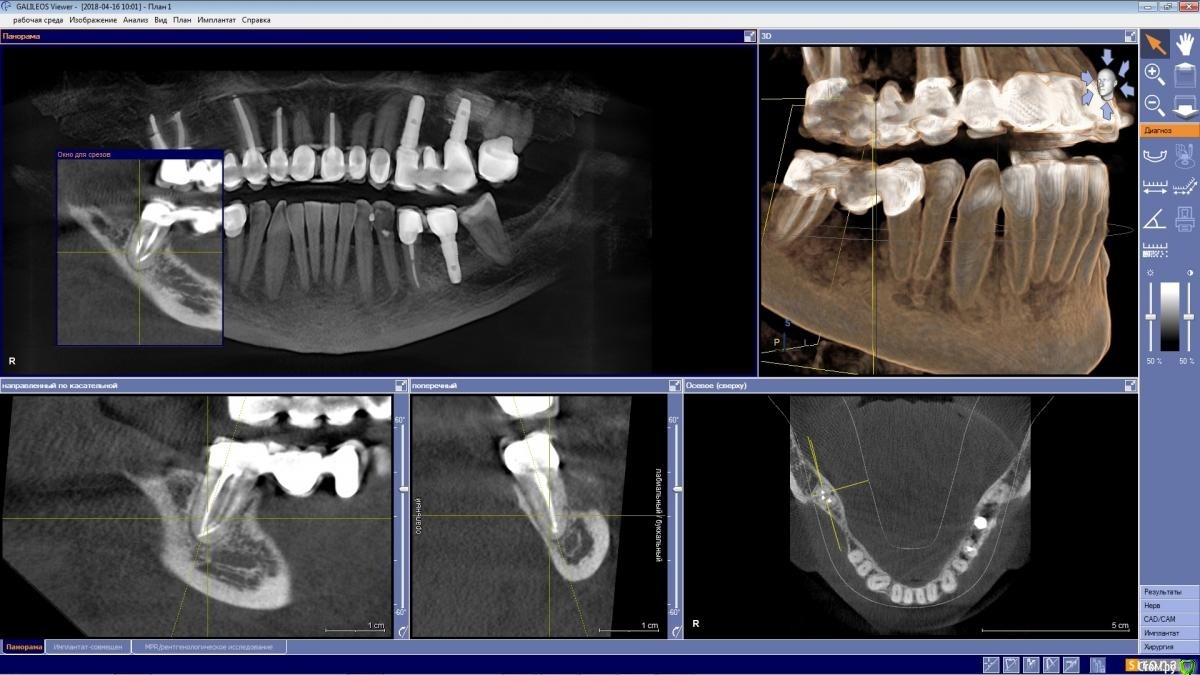

wladdX Опубликовано 25 октября, 2020 Поделиться Опубликовано 25 октября, 2020 КТ 04.2018. Я дополнительных каналов не увидел, может коллеги что рассмотрят. Ссылка на комментарий

ellenchik Опубликовано 26 октября, 2020 Автор Поделиться Опубликовано 26 октября, 2020 КТ 04.2018. Я дополнительных каналов не увидел, может коллеги что рассмотрят.1.jpg2.jpgСпасибо ,wladdX! Может врачи форумные еще что-то по снимкам подскажут. Ссылка на комментарий

St. Опубликовано 26 октября, 2020 Поделиться Опубликовано 26 октября, 2020 Да, в плане каналов все красиво. То есть все найдены и запломбированы на всю длину корня, и воспаления за пределами зуба не видно.Возможно, беспокоила десна Ссылка на комментарий